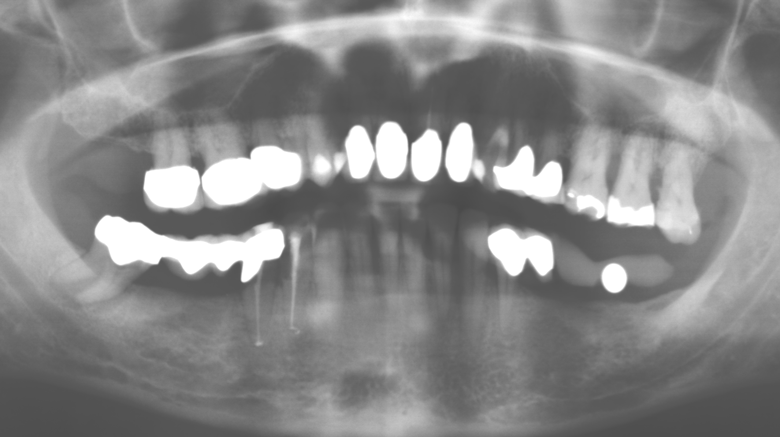

Un'assistenza standardizzata e regolare a misura di rischio nell'ambito di SPT è la chiave per il successo del trattamento clinico a lungo termine nei pazienti con situazione periodontale compromessa. Ciò è particolarmente vero per i pazienti a cui vengono applicati impianti dopo il trattamento parodontale completato con successo (Fig. 11a e b).